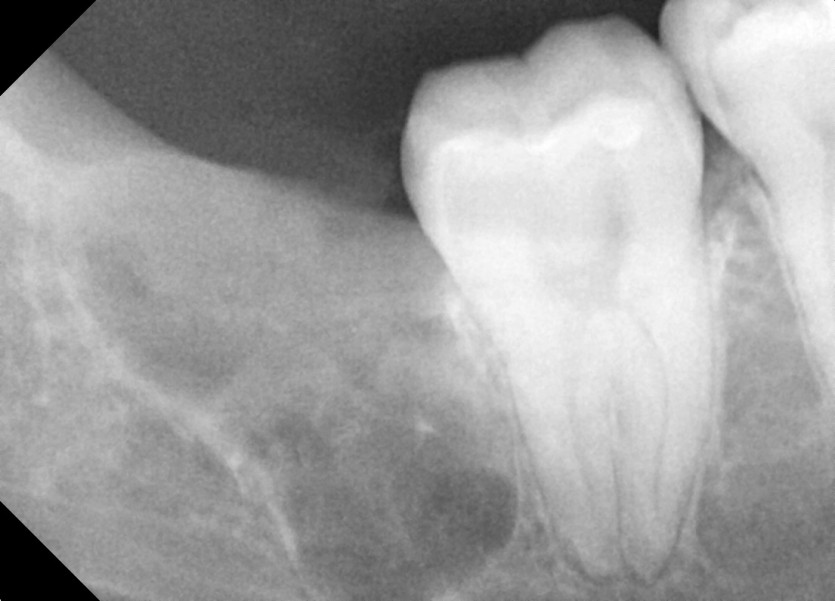

#18,48 사랑니 발치

구강 외과 전문의가 당일 발치했습니다.